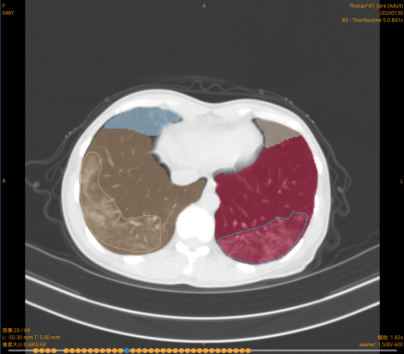

其次,“智能量化分析”功能实现了精确的病灶量化分析与动态评估,为病程进展提供量化指标与及时的风险预警,辅助影像科医生进行病变分期与病情严重程度的判断,并为临床及时采取针对性治疗方式提供依据。